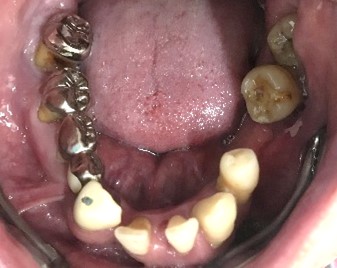

男性Iさん 50代(マグネット式入れ歯)

主訴

グラグラしている歯がある。歯並びをきれいにし、しっかり噛めるようになりたい。

治療内容

歯周病が進行し深刻な状態でした。保存することができない歯が上4本、下3本ありましたので、抜歯し、残った歯上4本、下7本の歯周病治療を徹底的にし、それらの歯を活用し上下マグネット式総入れ歯を入れました。

所感

治療前は、歯周病が進行し、重度に動揺している歯が4本あり、満足に食事ができない状況でした。マグネット式総入れ歯を装着後は、「なんでも思い通り噛むことができるだけでなく、歯並びもきれいになり、とても幸せです。」と、とても喜んでくださいました。

Before

赤丸は抜歯しました。上4本、下3本